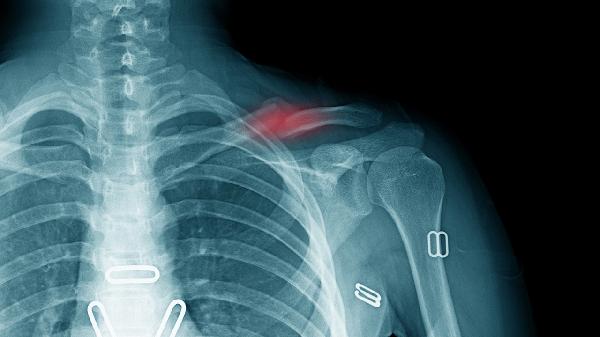

合并臂丛神经损伤需延迟至6周后锻炼。出现反射性交感神经营养不良时,应优先进行疼痛管理。二次移位风险高的粉碎性骨折需延长固定时间2-3周。